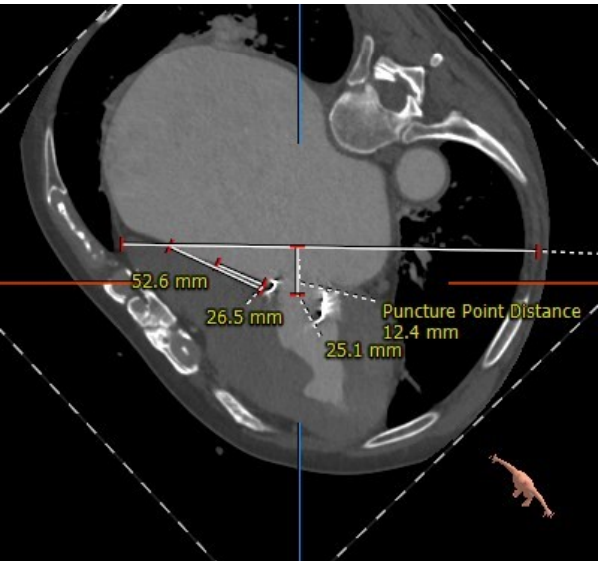

但该例患者CT分析显示,经股静脉—房间隔途径时,房间隔穿刺位置过低,难以实现输送系统自房间隔—左房—二尖瓣的通过,无法采用经股方式,在充分评估患者情况后,姜正明教授团队决定行经心尖途径入路。